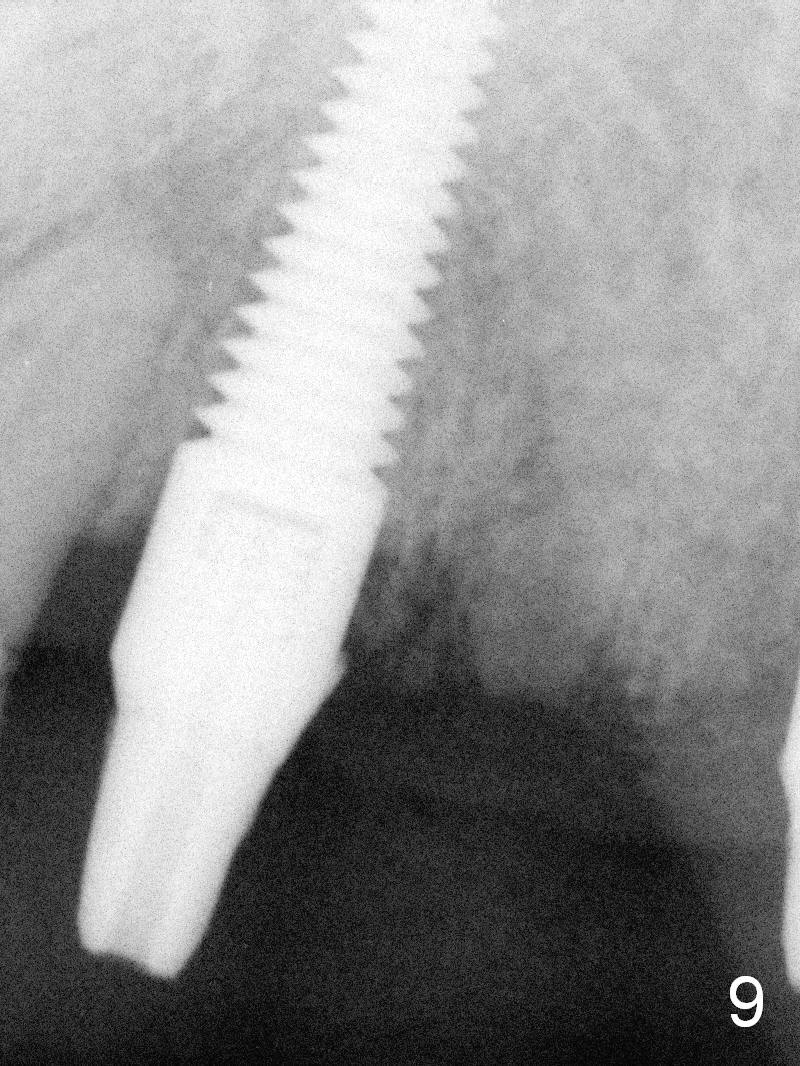

The patient returns for definitive restoration 3.5 months postop (Fig.9). Osteointegration appears to have occurred at #11.